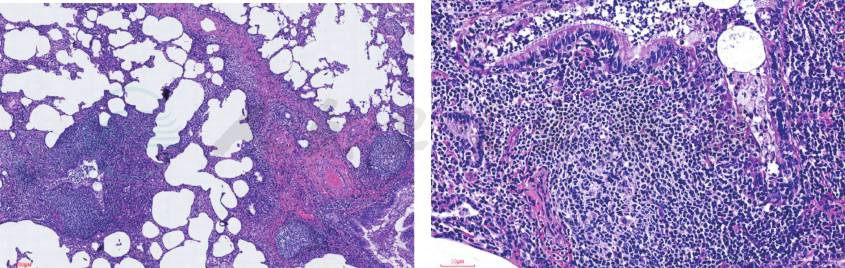

入院后完善相关检查,考虑支气管扩张患儿肺部铜绿假单胞菌等革兰氏阴性杆菌定植后感染较多见,经验性予头孢他啶抗感染,同时予大环内酯类抗生素口服抗感染治疗。入院后查血常规+CRP正常,血沉45mm/h(升高),LDH 847U/L(升高),肝肾功能、血清铁蛋白及降钙素原正常,呼吸道病毒抗体、肺炎支原体、衣原体、嗜肺军团菌阴性,痰培养呼吸道正常菌丛生长,未检出明确病原菌。入院后完善胸部HRCT检查,所见(图1)左肺上叶舌段、下叶及右肺下叶可见散在粟粒状渗出影及“树芽征”,右肺中叶见片状渗出影,右肺中、下叶部分支气管扩张、管壁增厚,部分管腔内见黏液栓。根据胸部CT表现,临床思考:①两肺散在粟粒状渗出影和小结节影以及“树芽征”,提示累及细支气管的炎症渗出或分泌物堵塞,考虑到患儿同时存在慢性鼻窦炎,需注意弥漫性泛细支气管炎的可能,予以完善副鼻窦CT及冷凝集试验;②存在结核感染可能,应详细询问排除结核接触史,并完善结核感染T细胞测定、肺泡灌洗液抗酸染色及结核分枝杆菌DNA定量等检查;③真菌感染表现不典型,可行真菌1,3-β-D葡聚糖试验辅助诊断;④注意肺囊性纤维化、原发性纤毛运动障碍及先天性免疫缺陷等少见病的可能,完善细胞体液免疫功能、血淀粉酶检测,亦需进行副鼻窦CT检查,同时在支气管镜检查中进行支气管黏膜活检电镜检查;⑤应继续完善病原学的检测,予以支气管镜检查及支气管肺泡灌洗。患儿入院第4天行支气管镜检查,术中发现患儿气道结构正常,右主支气管、右肺中叶及左主远端支气管内较多白色黏稠分泌物附着,阻塞部分支气管开口,予以吸引干净后在上述支气管开口处做支气管肺泡灌洗,回收灌洗液送培养和相关病原学检测。并分别在右肺中叶支气管、左主远端支气管开口取活检,送电镜纤毛检查。入院第5天,患儿咳嗽减轻,咳痰减少,肺部啰音减少。但前述各项检查中,除外副鼻窦CT平扫(图2)示全鼻窦炎,窦内分泌物密度较高,其余血清学检查、肺泡灌洗液检查、纤毛电镜检查及基因检查(罕见遗传病基因测序)均未见异常。与患儿及家属充分讨论后,于入院第13天行肺活检术,手术顺利,术后恢复可。肺组织病理检查(右肺)(图3)提示淋巴组织增生相关疾病(滤泡性细支气管炎,部分区域呈淋巴细胞间质性肺炎改变)。同时完善自身免疫疾病抗体全套检查,其中ANA 1:320(阳性),余抗体阴性。入院第19天患儿病情稳定出院,出院后长期口服小剂量红霉素抗炎,口服细菌溶解产物调节免疫功能,雾化吸入乙酰半胱氨酸化痰,并嘱每日体位引流及震动正压通气装置呼吸锻炼2~3次,风湿科及呼吸科定期随访。目前随访至出院后5个月,期间短时发热2次,未予特殊处理自行恢复,咳嗽咳痰好转,近2个月体位引流排痰量较前减少,活动耐力较前增加,随访6分钟步行试验达年龄预计值81.8%(病初56%),生长发育良好。

图3 右肺组织病理切片(HE染色,40倍及200倍)

大部分区域肺泡结构破坏,间质大量淋巴细胞浸润,局部淋巴滤泡形成,残留肺泡腔上皮细胞增生,部分支气管扩张,腔内见炎性黏液物

滤泡性细支气管炎。

诊断依据:①临床表现:间断发热、咳嗽、咳痰,肺部听诊有湿啰音;②肺HRCT:左肺上叶舌段、下叶及右肺下叶可见散在粟粒状渗出影及“树芽征”。右肺中、下叶部分支气管扩张、管壁增厚,部分管腔内见黏液栓;③肺组织病理检查(右肺)提示淋巴组织增生相关疾病(滤泡性细支气管炎,部分区域呈淋巴细胞间质性肺炎改变)。

滤泡性细支气管炎(follicular bronchiolitis)是一个组织病理学诊断,以细支气管壁伴有生发中心形成的淋巴样滤泡增生为特征。当肺内淋巴组织受到刺激时,在细支气管周围发生淋巴滤泡多克隆样增生,导致细支气管壁炎性增厚,细支气管管腔受压狭窄,形成滤泡性细支气管炎。常与慢性感染和炎症性气道疾病,例如囊性纤维化、支气管扩张、慢性误吸、结缔组织疾病、包括AIDS在内的免疫缺陷综合征有一定的相关性。主要发生于中年成人,罕见报道于儿童。多数滤泡性细支气管炎伴有基础疾病如结缔组织病,特别是类风湿性关节炎和干燥综合征(Sjögren syndrome),还可伴有免疫缺陷性疾病,如普通变异型免疫缺陷病和HIV感染,或者是过敏性肺炎等,原发性滤泡性细支气管炎较罕见。

病理表现为弥漫分布于细支气管周围具有相对原始生发中心的淋巴滤泡增生,伴有间质淋巴细胞浸润,可引起小气道阻塞。结合临床表现和影像学表现可诊断滤泡性细支气管炎。